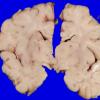

Familial erythrophagic lymphohistiocytosis (4)